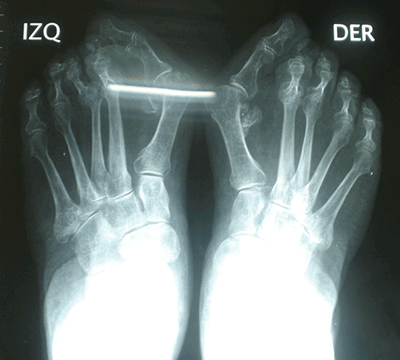

Caso 1: Hallux Valgus del Adulto